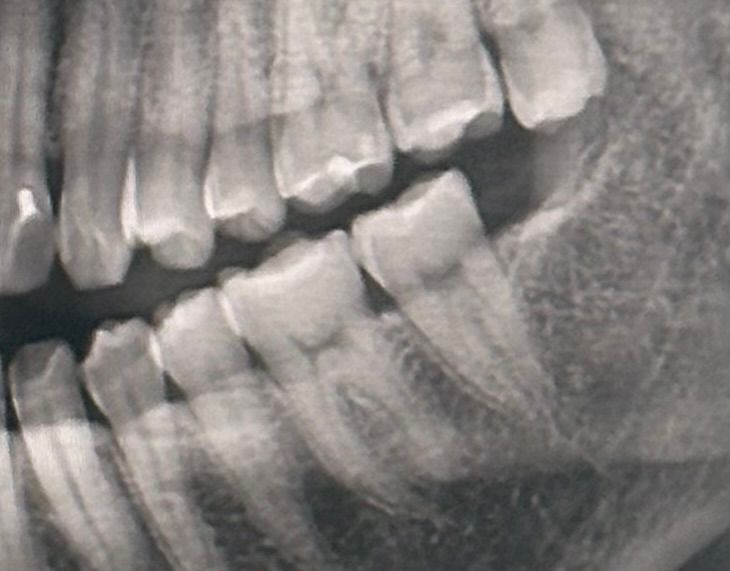

이거 충치일까요? ㅠㅠ 스케일링은 두 달전에 받았고 매일 치실 양치를 열심히 하는데 어느순간 검은선? 같이 보입니다.. 치과가기가 너무 무서워요 충치일까봐

엑스레이는 2주전 찍은 것 입니다